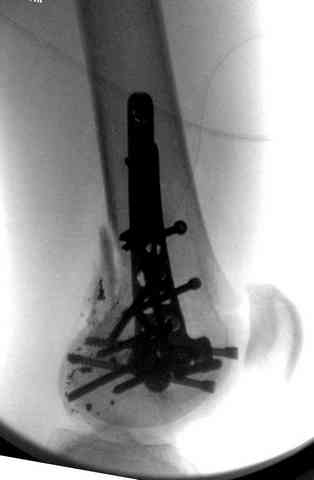

2 внутрисуставной перелом дистального бедра с удалением пули